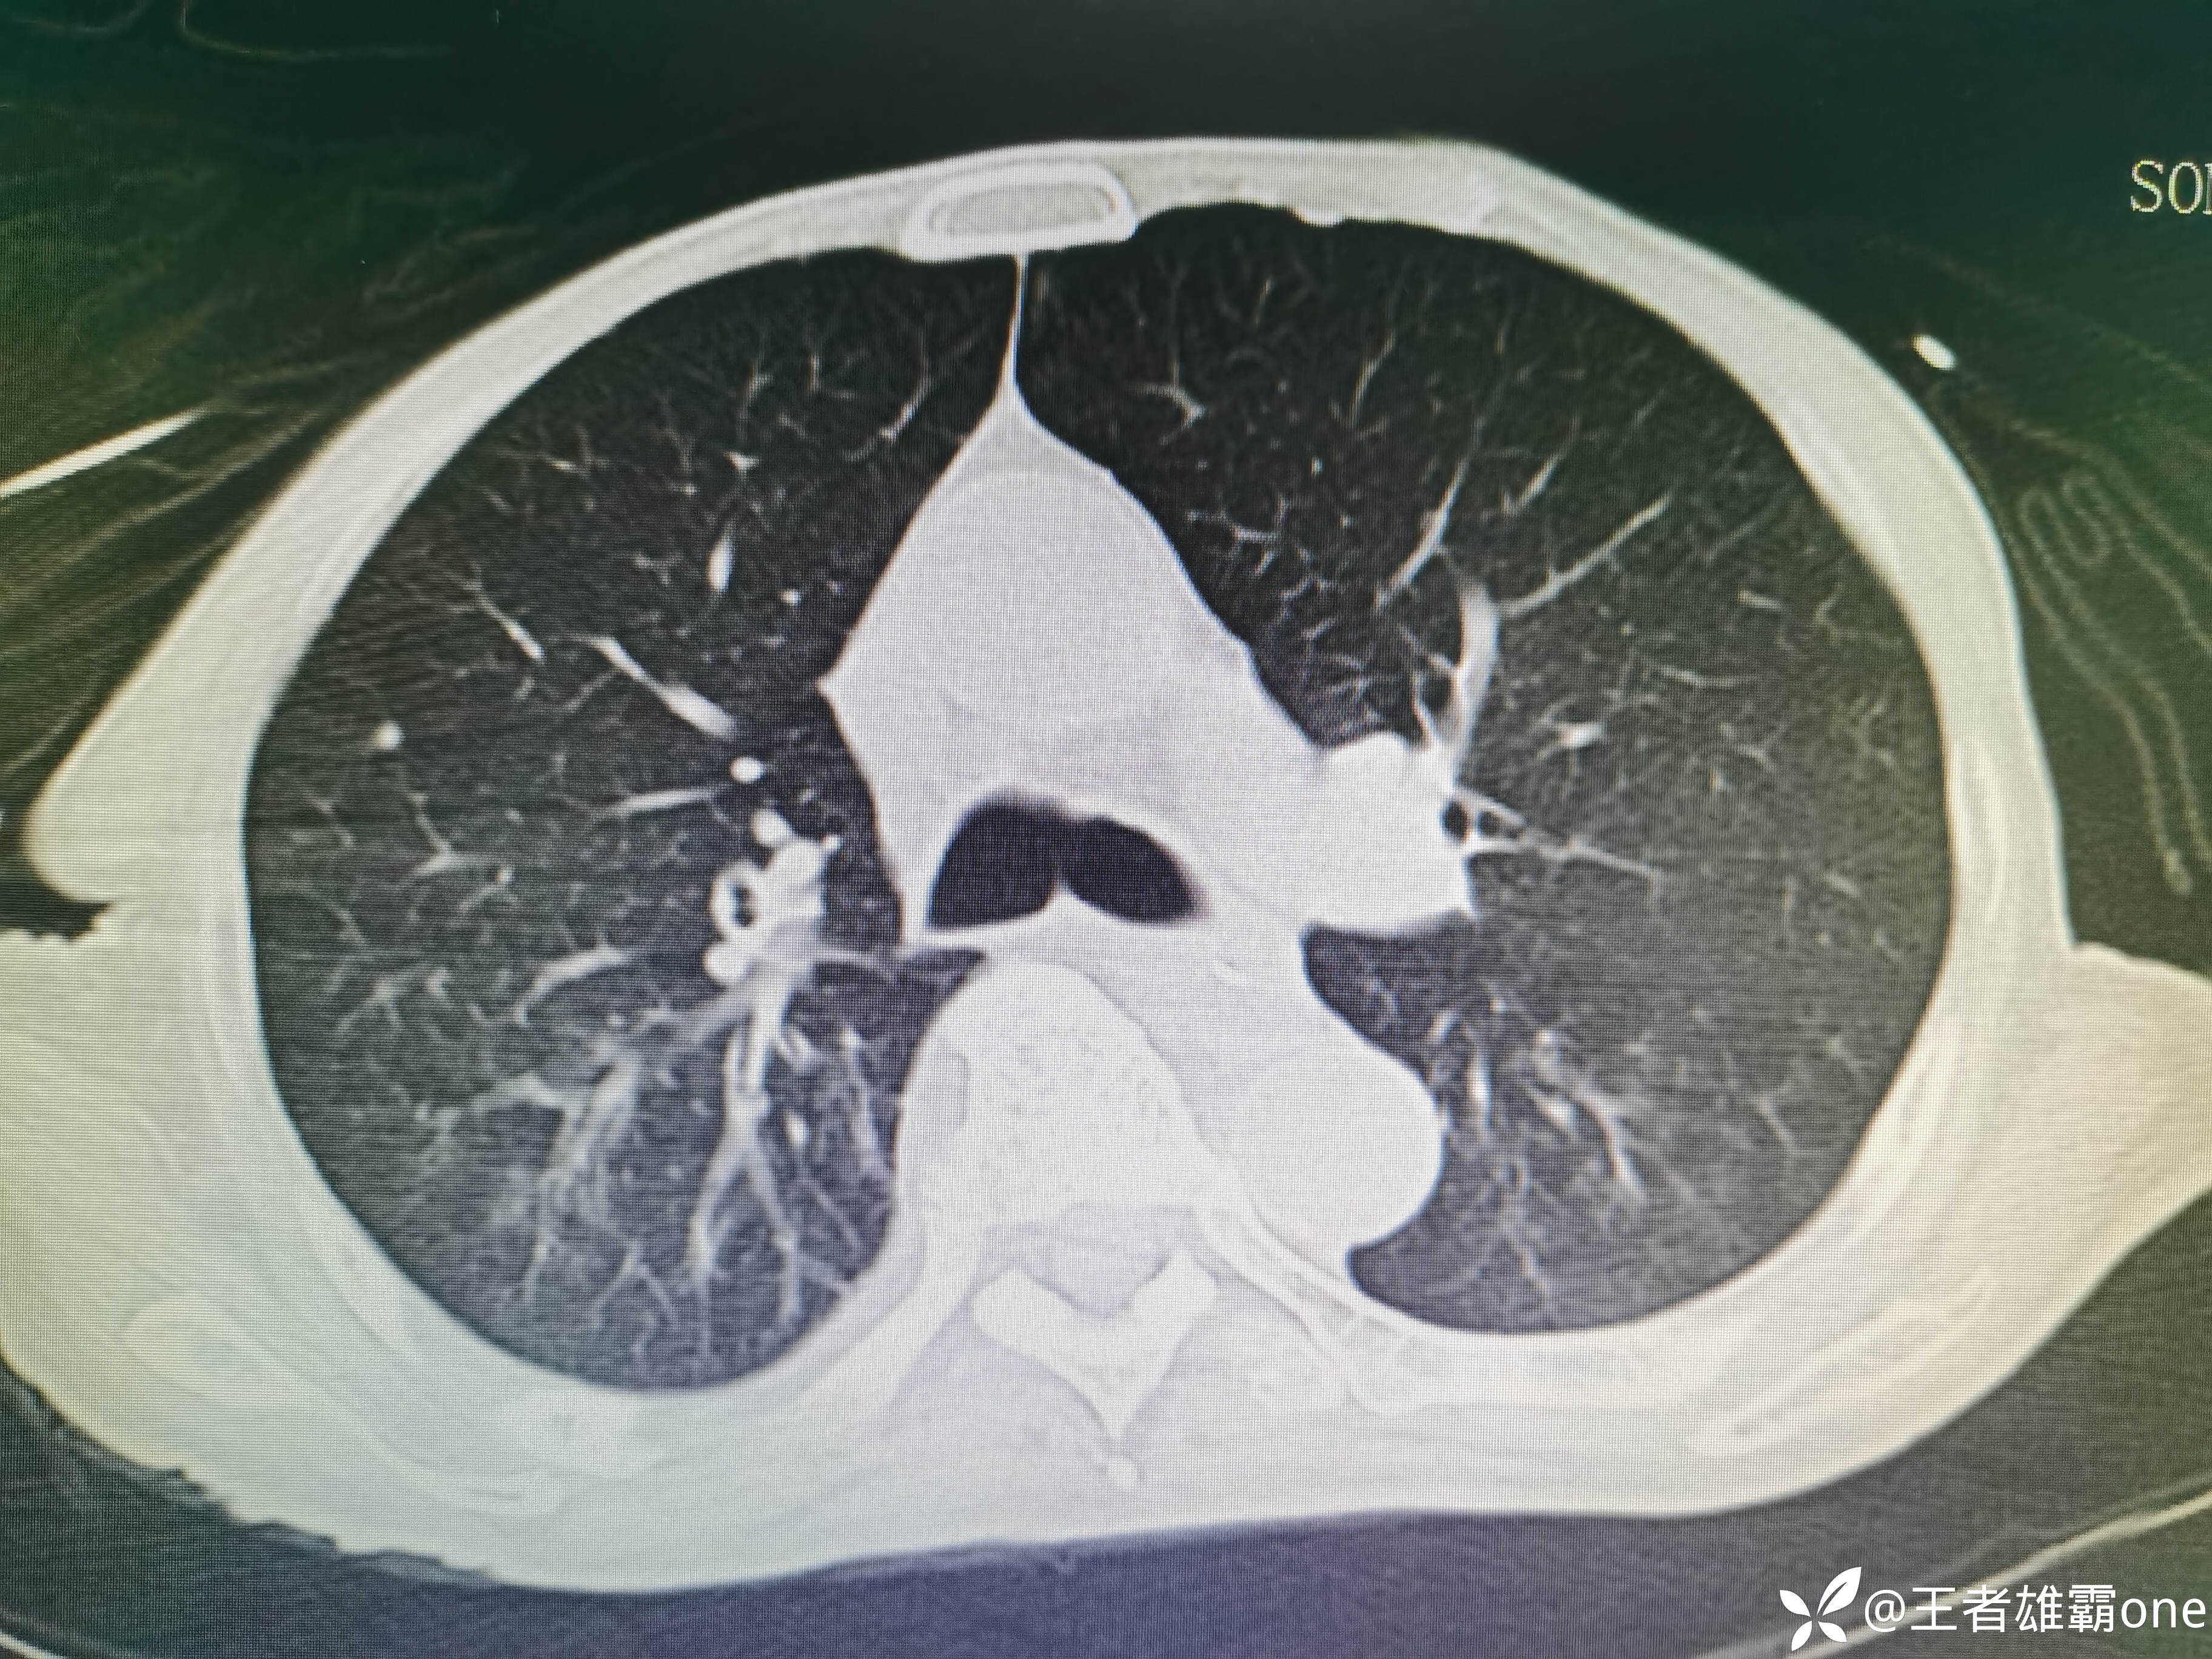

入院时胸部CT:

具体图片: